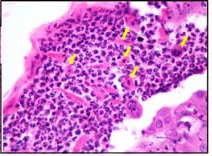

Figure 2: Histopathology |

Arrows showing acantholytic keratinocytes admised with neutrophills |

Surgical biopsy and histopathological examination of the skin remains the gold standard for diagnosis of pemphigus folieaceus. However, a definitive diagnosis cannot be reached in some instances due to the stage of the disease and the quality of the biopsy. Biopsies should be collected from sites directly adjacent to early pustules and vesiculopustules, immediately placed in formalin and submitted for microscopic examination. Subcorneal pustules with acantholytic keratinocytes is the hallmark lesion for diagnosis of pemphigus folieaceus. Note: Submitting multiple biopsies greatly increases the likelihood of finding a diagnostic lesion.Often, secondary pyoderma complicates the disease process. It is often recommended to treat the dog for pyoderma prior to collecting samples for surgical biopsy. We recommend submitting a complete clinical history which includes breed, age, distribution of lesions, clinical course and past history of treatment and underlying skin conditions.